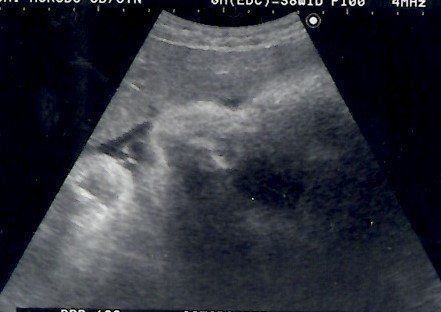

妊娠28週目のエコー写真 3D画像を撮影することを決意

健診を受けていた病院からもらうエコー画像は、ごく一般的な2Dタイプ。私は、この時期だけの赤ちゃんの姿を記念に残したかったことと、赤ちゃんが本当に元気に育っているのかをはっきりと確認したかったので、3D画像の撮影だけでも予約可能な産院を探すことを決意。この時すでに赤ちゃんがこれ以上大きくなると映りにくくなるというぎりぎりのタイミングでした。

妊娠29週目のエコー写真 3Dのエコー画像撮影にチャレンジ

わざわざ別の産院に出向き、高い料金を払って3D画像撮影に挑んだものの、なんと、撮影した時間帯の赤ちゃんはおなかに向かって後ろ向きにおねんね中。残念ながら期待していたような顔がわかる3D画像は撮影できませんでした。それでも、2D画像ではわからなかった腕や後ろ姿が鮮明に写っており、とても興奮しました。